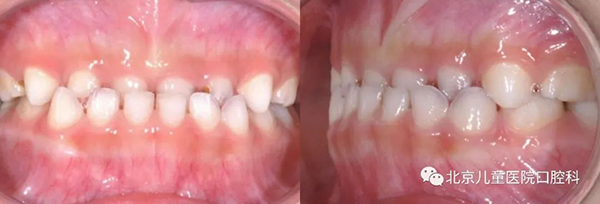

牙齿“地包天”,咬合时下前牙在上前牙外面